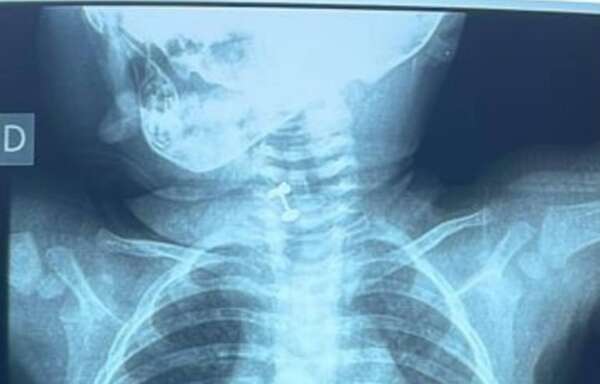

Médicos piden tener cuidado con objetos pequeños: una bebé de diez meses tragó su “primer arito”  - Nacionales - ABC Color

Una bebé de 10 meses tragó el regalo que le hicieron, su primer arito. En el Instituto Nacional de Enfermedades Respiratorias (Ineram), lograron extraer el objeto a tiempo. ...[Leer más]